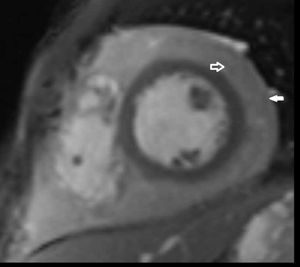

An 18-year-old Nigerian male with a history of previous exposure to tuberculosis, presented to our department for a mild, subcontinuous, fever and dyspnea.